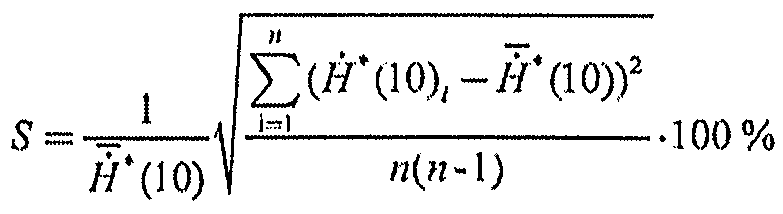

6.2. Среднее квадратическое отклонение среднего арифметического (далее - СКО среднего) результата измерений, S, %, для дозиметров, измеряющих МПД и МАД, рассчитывают по формулам (5, 6):

(5)

(6)

Для дозиметров, индицирующих коэффициент вариации и(или) статистическую погрешность результата измерений, можно считать, что СКО среднего равно коэффициенту вариации и(или) статистической погрешности.

6.3. Стандартную неопределенность, обусловленную источниками, имеющими случайный характер, %, принимают равной среднему квадратическому отклонению S, %, рассчитанному по формулам (5) или (6):